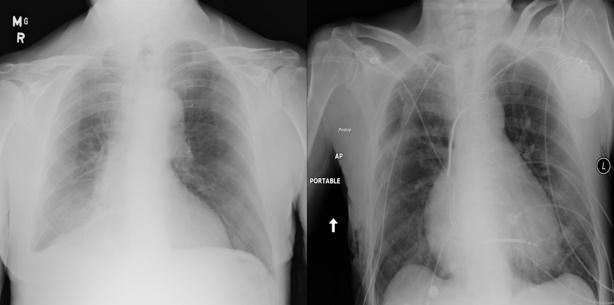

Fig.1 Normal(left), Infected (right) Fig.2 Fig.4 CNN Architecture[7]